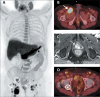

Objective: To investigate clinical, pathology, and imaging findings associated with inguinal lymph node (LN) metastases in patients with prostate cancer (PCa).

Materials and methods: This was a retrospective single-center study of patients with PCa who underwent imaging and inguinal LN biopsy between 2000 and 2023. We assessed the following aspects on multimodality imaging: inguinal LN morphology; extrainguinal lymphadenopathy; the extent of primary and recurrent tumors; and non-nodal metastases. Imaging, clinical, and pathology features were compared between patients with and without metastatic inguinal LNs.

Results: We evaluated 79 patients, of whom 38 (48.1%) had pathology-proven inguinal LN metastasis. Certain imaging aspects- short-axis diameter, prostate-specific membrane antigen uptake on positron-emission tomography, membranous urethra involvement by the tumor, extra-inguinal lymphadenopathy, and distant metastases-were associated with pathology-proven inguinal LN metastases (p < 0.01 for all). Associations with long-axis diameter, fatty hilum, laterality, and uptake of other tracers on positronemission tomography were not significant (p = 0.09-1.00). The patients with metastatic inguinal LNs had higher prostate-specific antigen levels and more commonly had castration-resistant PCa (p < 0.01), whereas age, histological grade, and treatment type were not significant factors (p = 0.07-0.37). None of the patients had inguinal LN metastasis in the absence of locally advanced disease with membranous urethra involvement or distant metastasis.

Conclusion: Several imaging, clinical, and pathology features are associated with inguinal LN metastases in patients with PCa. Isolated metastasis to inguinal LNs is extremely rare and unlikely to occur in the absence of high-risk imaging, clinical, or pathology features.